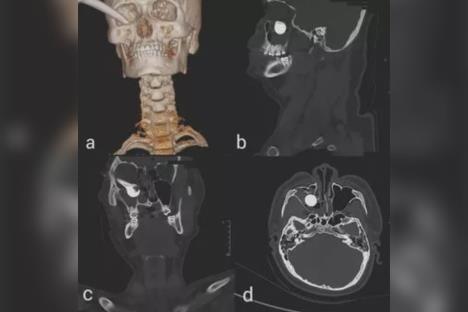

Drška od 17 centimetara ušla mu je samo malo levo od očne jabučice. Nakon pregleda, lekari su otkrili da je tinejdžerova mrežnjača zamagljena i oštećena. CT snimci su pokazali da je ručka motocikla dečaku probila donju očnu duplju i oštetila deo kosti oko nosa. Na sreću, osovina je promašila njegovu zenicu i živce, što znači da je za dlaku izbegao dugotrajno oštećenje oka.